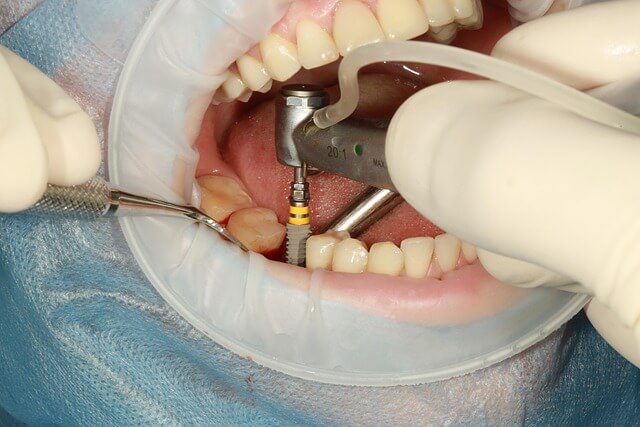

눈앞에 펼쳐진 상악동 거상술의 비밀, 초보자도 놀랄 사기급 꿀팁 대공개! 상악동 거상술은 윗턱 어금니 부위의 부족한 뼈를 인공뼈로 채워 임플란트 성공률을 획기적으로 높이는 핵심 시술입니다. 이 한 수술로 뼈가 얇아 임플란트가 어려웠던 문제를 단번에 해결할 수 있죠. 상악동 거상술은 풍부한 임상 경험과 숙련된 의료진의 손길이 필요하지만, 그만큼 확실한 결과를 약속합니다. 지금 바로 상악동 거상술 정보를 확인하고, 자신감을 갖고 건강한 미소를 만들어 보시기 바랍니다. 상악동 거상술, 더 이상 미루지 말고 집에서 편하게 알아보세요!

*많은 분들이 상악동 거상술로 삶의 질을 회복했습니다. 상악동 거상술은 전문가가 고도의 기술로 빈 공간에 뼈를 채워 넣어 단단한 지지대를 만들어 주는 시술로, 안정성을 높여 줍니다.